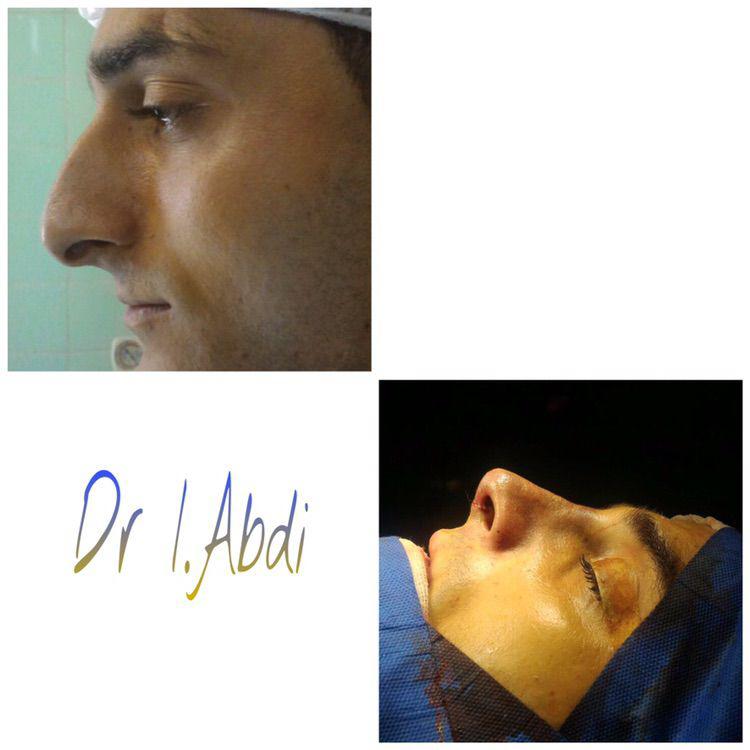

دکتر عیسی عبدی در رشت

دکتر عیسی عبدی در رشت

– متخصص جراحی فک , پلاستیک صورت و بینی

دکتر عیسی عبدی در رشت

جراحی فک , پلاستیک , صورت وبینی

جراحی ترمیمی و زیبایی فک و صورت و جمجمه و گردن